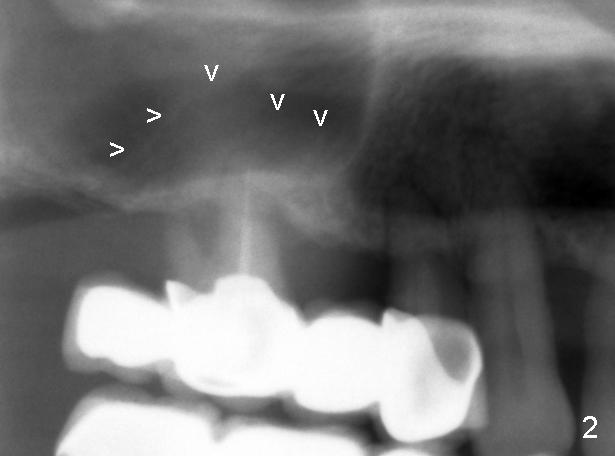

十天前我们初步讨论徐博那个疑难病例:右上4-7牙桥两到三度松动,如果问题在第一磨牙(图一:6),在4与5之间切断牙桥(图三虚线),拔除磨牙后即刻植牙(图三:大的红框)。虽然那里上颌窦底骨壁均为厚2mm左右,但是在那个磨牙牙根尤其是鄂侧根根尖处骨壁可能不止2mm,好像拱形(图二箭头,与图一对比)。所以第一磨牙处可以植入8x11mm植牙,不过需要做sinus

十天来对以上设计有双重心情,尤其是对那虚无缥缈的上颌窦里骨质(图二箭头),内心不踏实。